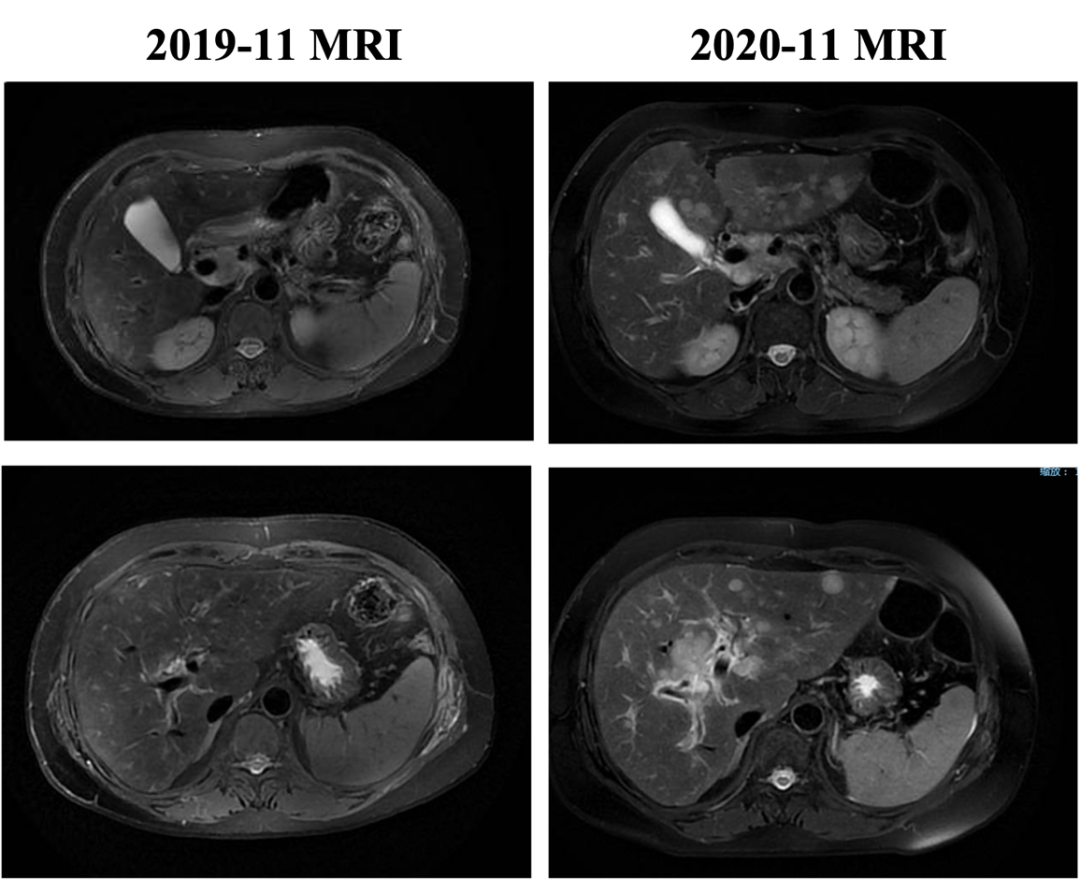

▌三线治疗:

入组MO28231临床试验,于2016-12-1开始行T-DM1治疗,具体:T-DM1 3.6mg/kg 237.6mg d1,Q21d。最佳评效PR。肝门区淋巴结自2019-6出现,逐渐增大,2019-11增大至29*22mm,考虑转移,判定为新发病灶PD出组,共治疗48周期,PD时间为2019-6,PFS为30月。不良反应:胆红素升高1级,血小板下降1级,疲劳1级,鼻出血1-2级,关节僵硬1级,手足麻木1级。

图4. 三线治疗